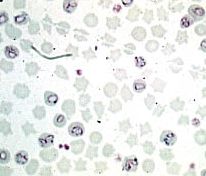

イソスポーラ属種(Isospora bahiensis)

オーシストは亜球形、ときには球形ないし広楕円形、無色に近く、おおきさは10~14 x 10~12(平均12 x 10)㎛

壁は平滑、無色

胞子形成時間は、30~37℃で12時間、室温で1~3日

犬、キツネ、ディンゴの小腸全域に寄生し、世界各地に分布します。